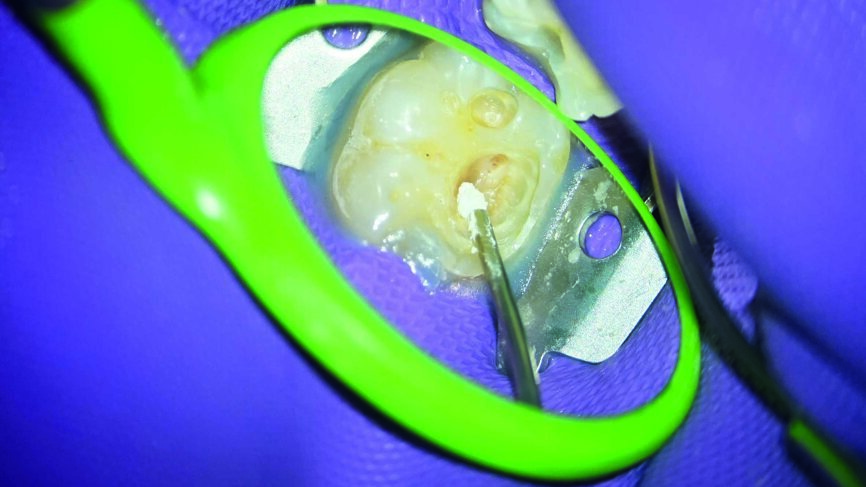

Ein 24-jähriger Patient kam mit vorübergehenden, provozierten Zahnschmerzen an Zahn #19 in die Zahnklinik (Abb. 1). Die Diagnose lautete reversible Pulpitis. Die Zahnfäule wurde unter kompletter Isolation entfernt, wobei es zweimal zur Freilegung der Pulpa mit minimalen Blutungen kam (Abb. 2). Die Blutungen wurden gestoppt, indem 10 Sekunden lang ein mit steriler Salzlösung getränkter Wattebausch auf die Stelle gedrückt wurde. Die Mundhöhle wurde mit 2,5% Natriumhypochlorit desinfiziert (Abb. 3), anschliessend wurde weißes MTA (Produits Dentaires) als Mittel zur unmittelbaren Pulpa-Überkappung eingesetzt (Abb. 4). Um sicherzustellen, dass das MTA korrekt eingesetzt wurde, kam das MAP-System für Dentalmaterialien (Produits Dentaires) zur Anwendung. Mit diesem System kann der Klinikarzt das Material exakt an der Expositionsstelle anbringen. Somit wird eine Verunreinigung der Dentinwände verhindert, die mit der Zeit eine Pigmentierung infolge des verwendeten Materials aufweisen könnten (Abb. 5 und 6). Sobald das MTA auf die Expositionsstellen der Pulpa und die tieferliegenden Teile des Pulpakammerdachs aufgetragen wurde, kam eine lichthärtende Kalziumhydroxidpaste zum Einsatz, um das Material zu schützen (Abb. 7), das Klebeverfahren durchführen und die abschliessende Zahnreparatur in derselben Sitzung vornehmen zu können (Abb. 8 und 9). Sieben Tage nach dem Verfahren war der Patient komplett symptomfrei und der Zahn reagierte normal auf Sensitivitätstests. In solchen klinischen Situationen ist davon auszugehen, dass zwischen sechs und neun Monaten nach dem Verfahren die Bildung von Kalkgewebe unter dem Überkappungsmaterial in Röntgenaufnahmen nachgewiesen werden kann. (7)